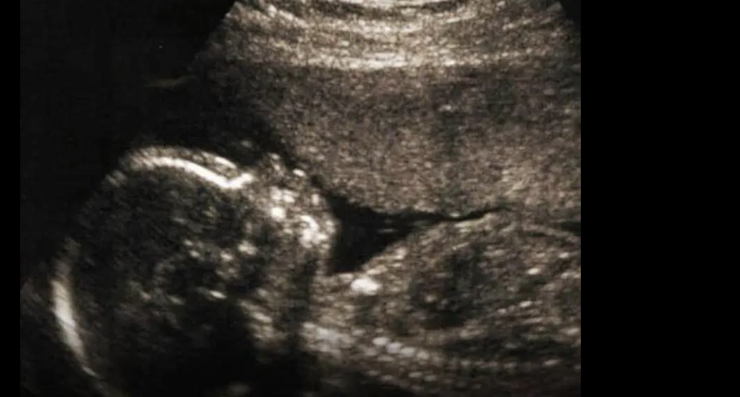

La ricerca suggerisce che il microbiota della madre abbia un’influenza maggiore rispetto a quello del bambino nello sviluppo dell’autismo.

Un elemento cruciale di questo meccanismo potrebbe essere una molecola prodotta dal sistema immunitario, chiamata interleuchina-17a, o IL-17a. Questa molecola è nota per il suo ruolo in malattie come la psoriasi, la sclerosi multipla e l’artrite reumatoide, e per contribuire alla difesa contro le infezioni fungine. Tuttavia, sembra anche influenzare lo sviluppo del cervello prima della nascita.

«Per quanto riguarda la traslazione del nostro lavoro sull’uomo, credo che il prossimo passo fondamentale sarà identificare le caratteristiche del microbioma nelle donne in gravidanza che possano essere correlate al rischio di autismo», ha affermato Lukens. «L’aspetto davvero importante sarà capire quali strumenti possiamo usare per modulare efficacemente e in sicurezza il microbioma materno.»